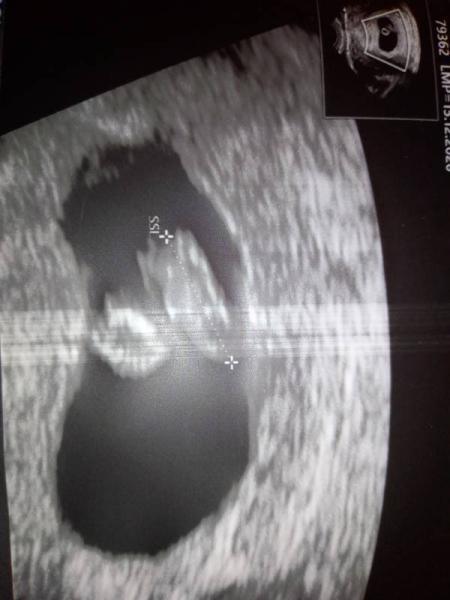

Laut meiner Berechnung meiner Periode und Eisprung (der aber für mich unsicher zu berechnen ist) müsste ich eigentlich 6+3 sein, aber heute beim Frauenarzt hat das Gerät 7+1 angezeigt. Ich finde aber das der Embryo mega merkwürdig aussieht, also so schmal... Herzaktivität und Durchblutung vom Embryo ist aber da... Frauenärztin meint ich soll in zwei Wochen wieder kommen und dann bekomme ich den Mutterpass. Blutuntersuchungen erfolgten... Hatte im Juni 2021 eine FG, deshalb bin ich unsicher.

Hallo, meiner von 7.0 sieht so aus. Also nicht so viel anders. Bei dir wurde nicht rein gezoomt, da erkennt man es halt nicht so gut. Aber solange alles andere passt, würde ich mir keine Gedanken machen. Vielleicht bist du ja irgendwo zwischen den beiden Zeit so 6.5. Dann sieht man eh etwas weniger als bei meinem. Wünsche dir viel Glück.